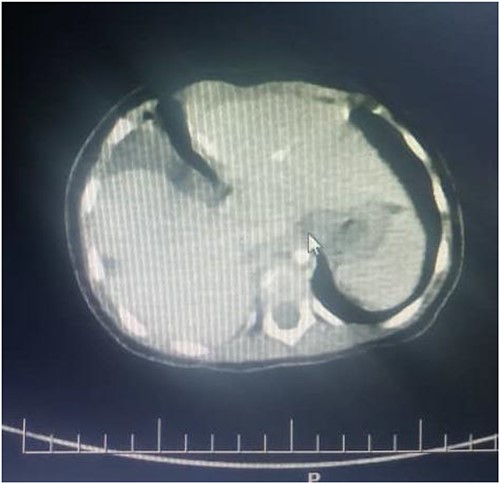

Thus, the tube thoracostomy with under water seal drainage was performed and supportive oxygen therapy was initiated accordingly. In the second day postadmission, the respiratory symptoms resolved and she was weaned off oxygen and other supportive therapies were reduced. Later a whole-body CT scan was performed and admitted in Paediatric Surgery ward in Muhimbili National Hospital. The CT scan revealed a hypodense fluid collection on the right hemithorax, 33HU associated with ipsilateral pulmonary atelectatic changes, discontinuity of the right hemidiaphragm with intrathoracic herniation of the liver that appeared to be normal in size. Nevertheless, the child was in good condition, without respiratory distress or bowel obstruction.

Figures 2 and 3 axial views of thoraco-abdominal CT image taken before laparotomy revealing a ruptured diaphragm of a 1-year-old post trauma patient with reduced right lung volume of expansion.